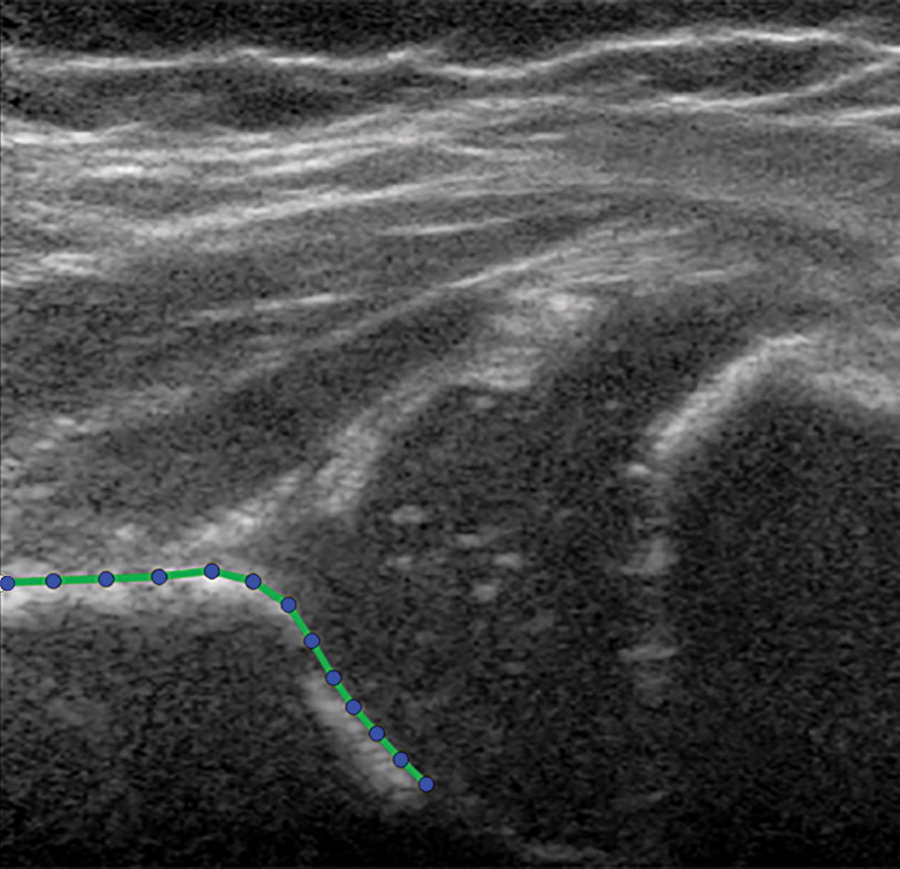

Une technique décrite dans un article de la Revue Radiology et utilisant des images échographiques pour déterminer la profondeur et la forme du cotyle de la hanche peut prédire avec précision l’évolution d’une dysplasie de hanche chez les nourrissons. Les chercheurs ont utilisé la modélisation statistique des formes pour améliorer le diagnostic prédictif, ce qui pourrait significativement réduire les surtraitements pour cette pathologie.

Le système de classification Graf est couramment utilisé pour évaluer la dysplasie de la hanche, mais il a des limites. Les patients sont classés par groupes, en fonction de l'angle acétabulaire sur les images échographiques. Cet angle est dérivé de la profondeur et de la forme du cotyle de la hanche où s'adapte la tête du fémur. Le système Graf présente une grande variabilité et une faible concordance dans toutes les mesures de dysplasie de la hanche rapportées, la qualité de l'image échographique et l'apparence anatomique de l’articulation pouvant être affectées par le positionnement de la sonde.

Le système de classification Graf est couramment utilisé pour évaluer la dysplasie de la hanche, mais il a des limites. Les patients sont classés par groupes, en fonction de l'angle acétabulaire sur les images échographiques. Cet angle est dérivé de la profondeur et de la forme du cotyle de la hanche où s'adapte la tête du fémur. Le système Graf présente une grande variabilité et une faible concordance dans toutes les mesures de dysplasie de la hanche rapportées, la qualité de l'image échographique et l'apparence anatomique de l’articulation pouvant être affectées par le positionnement de la sonde.

La modélisation statistique de la forme par ultrasons est une méthode alternative qui quantifie la forme de l'image de la hanche avec plusieurs points de référence qui ont chacun une coordonnée X et une coordonnée Y dans l'image échographique 2D. Elle offre des avantages potentiels par rapport aux modèles prédictifs existants. « En quantifiant l'image de la hanche avec une modélisation statistique de la forme, beaucoup plus de données sont extraites des images échographiques par rapport aux méthodes actuelles utilisées », poursuit le Dr Sakkers.

Dans cette étude, le Dr Sakkers et ses collègues ont analysé le pouvoir prédictif de la technique chez 97 nourrissons atteints de dysplasie stable de la hanche. Ils ont développé une modélisation statistique de la forme sur des images échographiques de base, puis ont corrélé le modèle avec une dysplasie persistante de la hanche à l'échographie après 12 semaines de suivi et une dysplasie résiduelle de la hanche sur les radiographies pelviennes vers l'âge d'un an. Les résultats ont montré que la modélisation statistique de la forme prédisait avec précision quelles hanches étaient devenues normales ou restaient dysplasiques. Ce processus a également identifié les hanches qui ont bénéficié d'un traitement avec le harnais Pavlik, une attelle souple qui favorise le développement normal de l'articulation de la hanche.